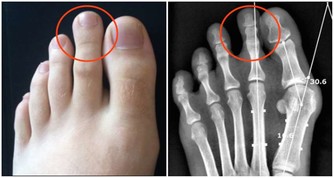

可樂等碳酸飲料及快餐等加工食品含有大量的磷,會妨礙人體吸收鈣,不利骨骼健康。